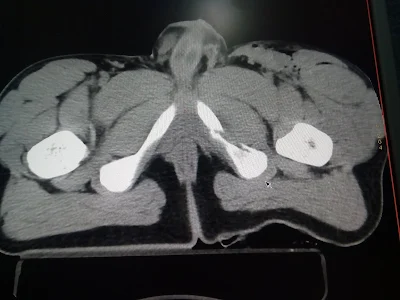

TRAUMATISMO PELVICO SEVERO LESIÓN DE ARTERIA ILIACA IZQUIERDA POR ATROPELLAMIENTO

PACIENTE ADOLESCENTE DE 15 AÑOS DE EDAD DEL SEXO MASCULINO, EL CUAL INGRESA AL ÁREA DE URGENCIAS POSTERIOR A SER ATROPELLADO POR CAMIÓN, SE DETECTA TRAUMATISMO SEVERO PÉLVICO, CHOQUE HEMORRÁGICO INTERNO IV GRADO, HEMATOMA PULSÁTIL EN INGLE IZQUIERDA CON INSUFICIENCIA ARTERIAL DE LA EXTREMIDAD, SE TOMA TOMOGRAFIA SIMPLE POR LOS MEDICOS DE URGENCIAS SIN MEDIO DE CONTRASTE CON HALLAZGOS DE FRACTURA PÉLVICA, EL PACIENTE SE SOMETIÓ DE MANERA URGENTE A LAPAROTOMIA Y SE ENCONTRÓ A NIVEL VASCULAR DESGARRO Y PÉRDIDA DE LA CONTINUIDAD DE ILIACA COMÚN A SU PASO A ILIACA EXTERNA CON SANGRADO Y HEMATOMA EXPANSIVO, TROMBOSIS DISTAL DE ILIACA, EL JOVEN SE SOMETIÓ A COLOCACIÓN DE INJERTO DE SAFENA INVERSA DE ILIACA IZQUIERDA Y PREVIA TROMBÉCTOMIA DISTAL DE VASOS FEMORALES, POPLITEOS Y TIBIALES RECUPERANDO FLUJOS DISTALES DE LA EXTREMIDAD PELVICA IZQUIERDA, POSTERIORMENTE PASÓ A TERAPIA INTENSIVA EN GRAVEDAD EXTREMA, ESPERANDO SER ESTABILIZADO DE SUS FRACTURAS POR ORTOPEDIA.

PACIENTE EN QUIRÓFANO INGRESADO